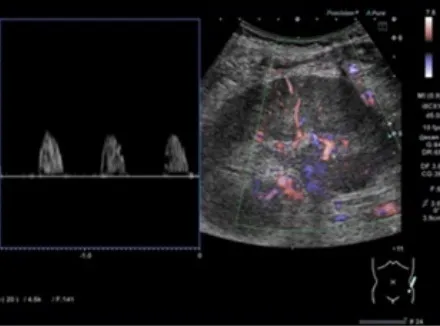

Uma causa incomum de hematúria glomerular intermitente!

Uma causa incomum de hematúria glomerular intermitente!